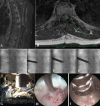

Results: Collectively, 19 cases described endoscopic spine surgery for spinal oncologic care. Endoscopic spine surgery has been employed for the care of patients with spinal tumors under the following 4 circumstances: (1) to obtain a reliable tissue diagnosis; (2) to serve as an adjunct during traditional open surgery; (3) to achieve targeted debulking; or (4) to perform definitive resection. These cases employing endoscopic techniques highlight the versatility of this approach and its utility when applied to the right patient and with an experienced surgeon.